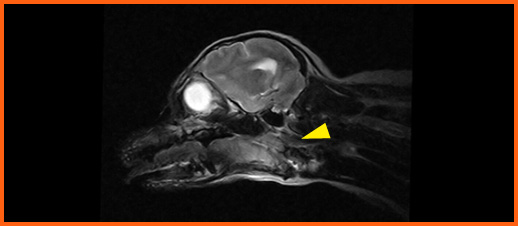

我們提供留院服務並擁有相應的治療設施,亦是小數備有CT電腦掃描及MRI磁力共振等大型醫療儀器的診所及醫院。